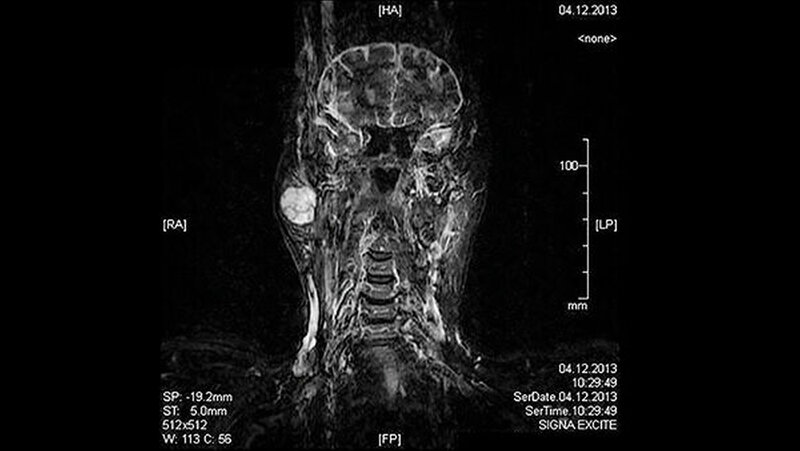

Eine 81-jährige Patientin wurde bei einer anamnestisch vor drei Jahren erstmals aufgefallenen und seither größenprogredienten Schwellung präaurikulär rechts (Abbildungen 1 bis 3) mit der Bitte um Weiterbehandlung an die Klinik für Mund-, Kiefer- und Gesichtschirurgie der LMU München überwiesen. Die alio loco durchgeführte bildgebende Diagnostik mittels MRT hatte einen abgegrenzten Prozess in der rechten Glandula parotidea gezeigt (Abbildungen 4 und 5). In der Zusammenschau der klinischen und der radiologischen Befunde wurde die Verdachtsdiagnose eines pleomorphen Adenoms im Bereich der Glandula parotis rechts gestellt.